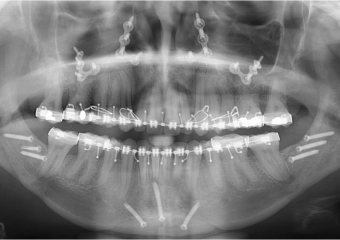

Raio x inicial